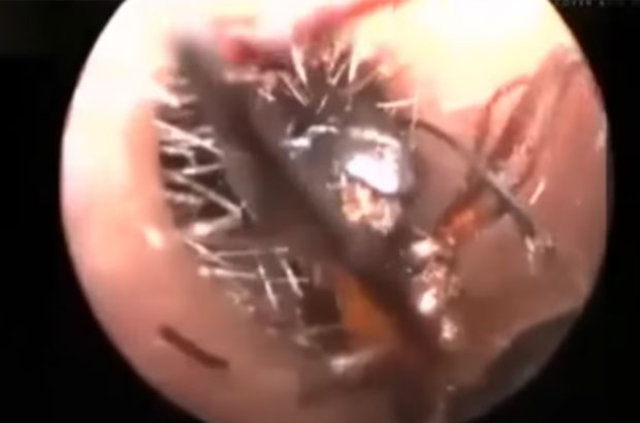

Endoskopik kamerayla çekilen görüntülerde doktorlar Shreya'nın kulağından, ölü karıncalar çıkarıyor. Küçük kızın çaresiz anne ve babası her yolu denediklerini ancak karıncalardan kurtulamadıklarını dile getirdiler.

Kulak Burun Boğaz Hastalıkları Uzmanı Dr. Jawahar Talsania, "Yapılabilecek tüm taramaları yaptık. MRI ve CT taramalarına rağmen her şey normal görünüyor. Küçük Shreya'nın kulaklarında hiçbir anormallik bulamadık.

Karıncaların bazen ısırmaları dışında küçük kız hiçbir acı çekmiyor. Kulak kanallarında herhangi bir hasar da tespit etmedik" açıklamasında bulundu.